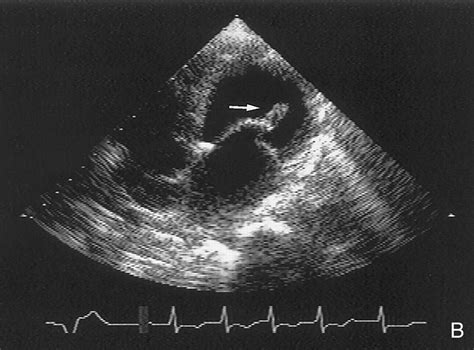

The gold standard for diagnosis is Echocardiography. Specifically, a Transesophageal Echocardiogram (TEE) provides the most detailed view of the valve structures and the flapping leaflet. It allows the medical team to see the ruptured muscle and the severity of the backflow (regurgitation) in real-time.